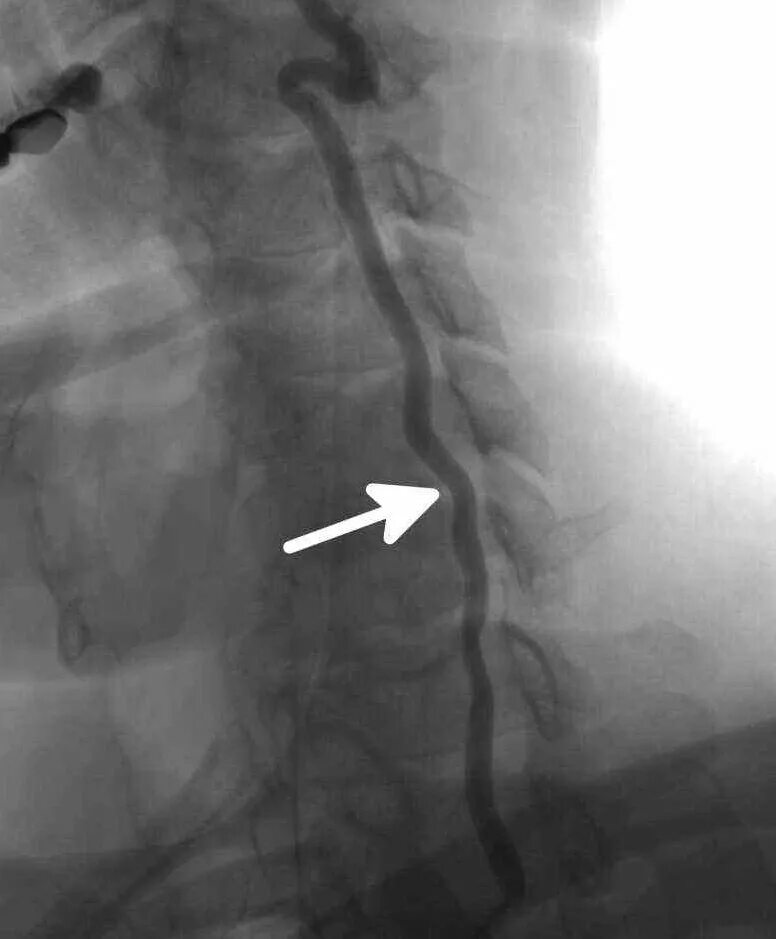

Деформация хода обеих